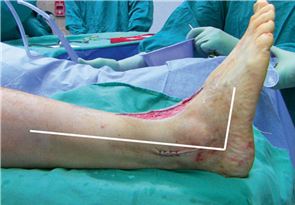

Clinical & Radiographic Imaging Archive

Clinical Image